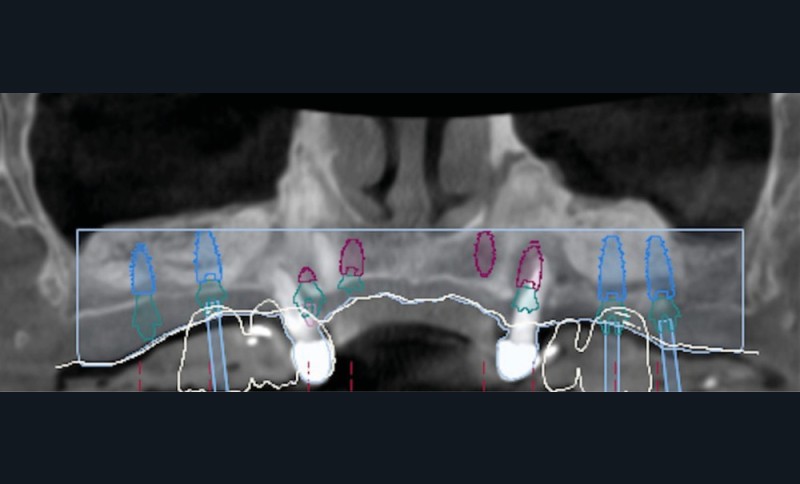

Le matching classique avec les fichiers STL et Dicom fut imprécis. La technique inspirée du « double scan » à l’aide de points radio-opaques sur la PAP provisoire maxillaire et d’un double CBCT a permis d’obtenir un matching extrêmement précis et la conception d’un projet prothétique numérique (Nemotec) associé à un Smile design (fig. 2). La modélisation 3D et le CBCT ont permis d’élaborer une planification implantaire, des guides à étages et un bridge complet provisoire en PMMA usiné (Biotech). La planification de 8 implants au niveau des 7/6/4/3 en fonction du volume osseux disponible et du projet prothétique virtuel a confirmé la possibilité de proposer un traitement sans greffe antérieure (fig. 3).